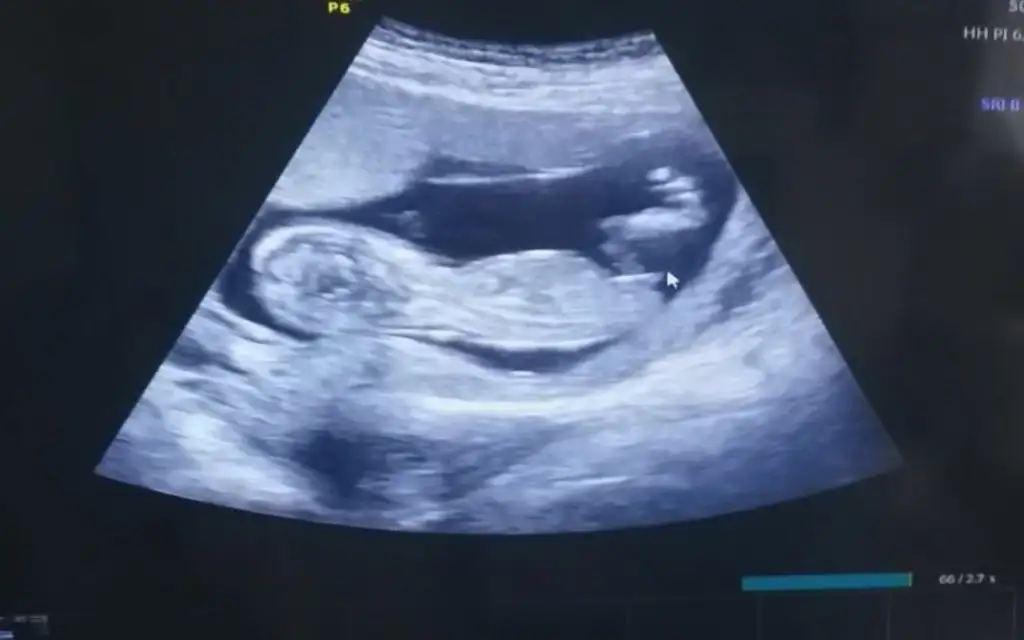

Kız görünüyorMrb 12+4 ben de tahmin alabilir miyim?